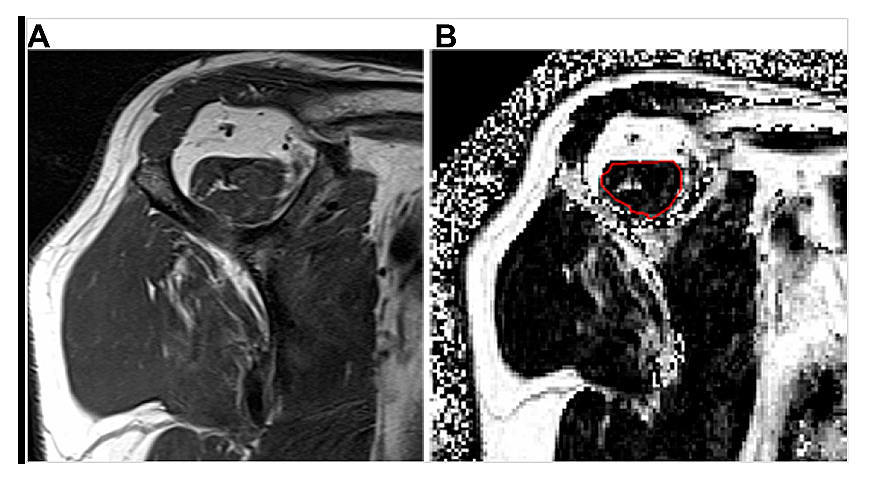

Rotator Cuff ImagingImaging is central for establishing the clinical diagnosis and prognosis for patients presenting with either traumatic acute-onset shoulder dysfunction or non-traumatic shoulder disorders which are not self-limited [22,44,45]. Magnetic resonance imaging (MRI) is the leading imaging modality in the United States to provide definitive imaging evaluation of patients with symptomatic shoulder dysfunction and is a valid and reliable method for diagnosing and characterizing the pattern of RC tear (Figure 1) [20,42,46–48]. MRI also provides concurrent prognostic information about the degree of intramuscular fatty infiltration associated with RC tear, a critical factor that influences orthopaedic surgeons’ clinical decision-making regarding patients’ eligibility to receive RC repair (RCR) surgery (Figure 2) [20,42,46–50]. RC tear is associated with structural changes in the corresponding muscle belly related to intramuscular proliferation of adipose cells and inflammation, fibrosis and apoptosis of myofibers leading to global muscle atrophy and dysfunction [51–53]. Animal and human models of RC tear show that intramuscular fatty infiltration is inversely related to muscular contractile force at the rotator cuff and does not improve after RCR surgery [20,51,54]. During initial steps of pre-operative evaluation, imaging metrics of RC muscle quality are critical, as advanced RC intramuscular fatty infiltration is a relative contraindication to RCR surgery and is associated with poor postsurgical outcomes [46,48–50].

Figure 2. Examples of rotator cuff muscle fatty infiltration classification on magnetic resonance imaging (MRI). (A) Oblique sagittal T1-weighted MRI shows a supraspinatus muscle with streaks of internal fat, consistent with semi-quantitative Goutallier grade 1 fatty infiltration. (B) Quantitative oblique sagittal 6-point Dixon fat fraction map MRI following manual image segmentation calculates an amount of 10.5% supraspinatus muscle fatty infiltration within the region of interest (red circle).